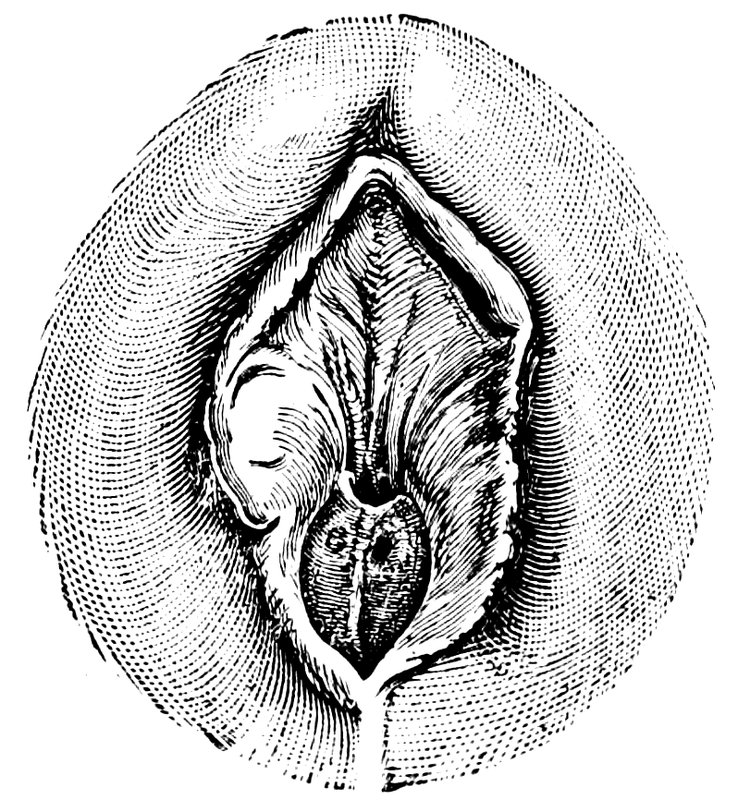

| 12. | Female external genital organs of a virgin | 54 |

| 13. | The external genital organs of a virgin | 55 |

| 48. | The female pudendum, or vulva, with the labia majora | 204 |

| 49. | Vestibule of the vagina, with the labia minora or nymphæ, etc | 205 |